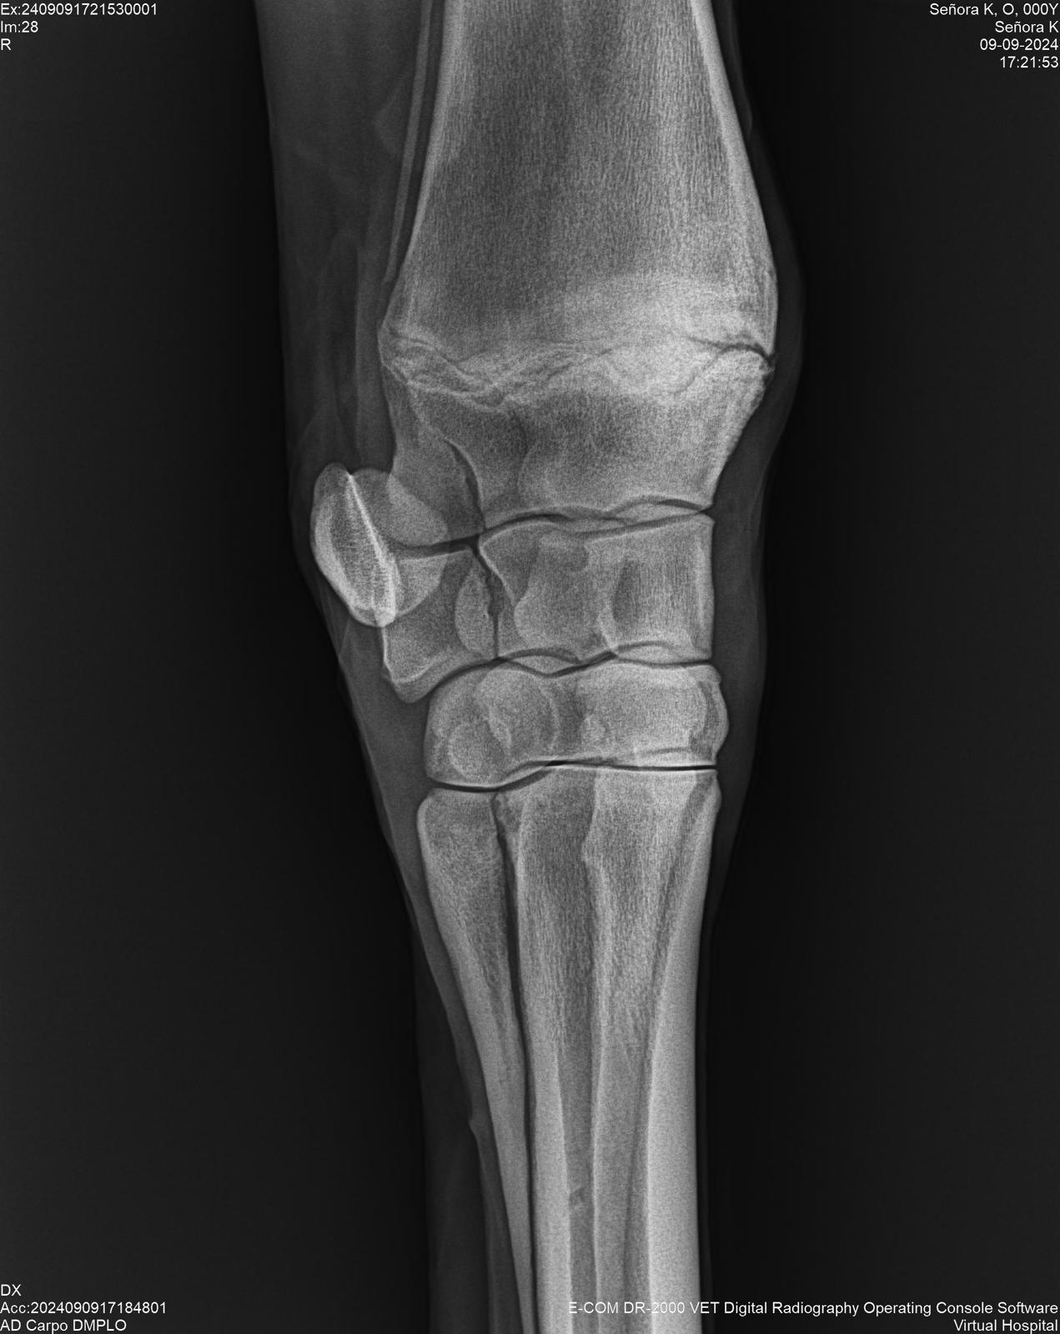

LOTE 44, SEÑORA K

Identificador: #291147-

Generacion 2022